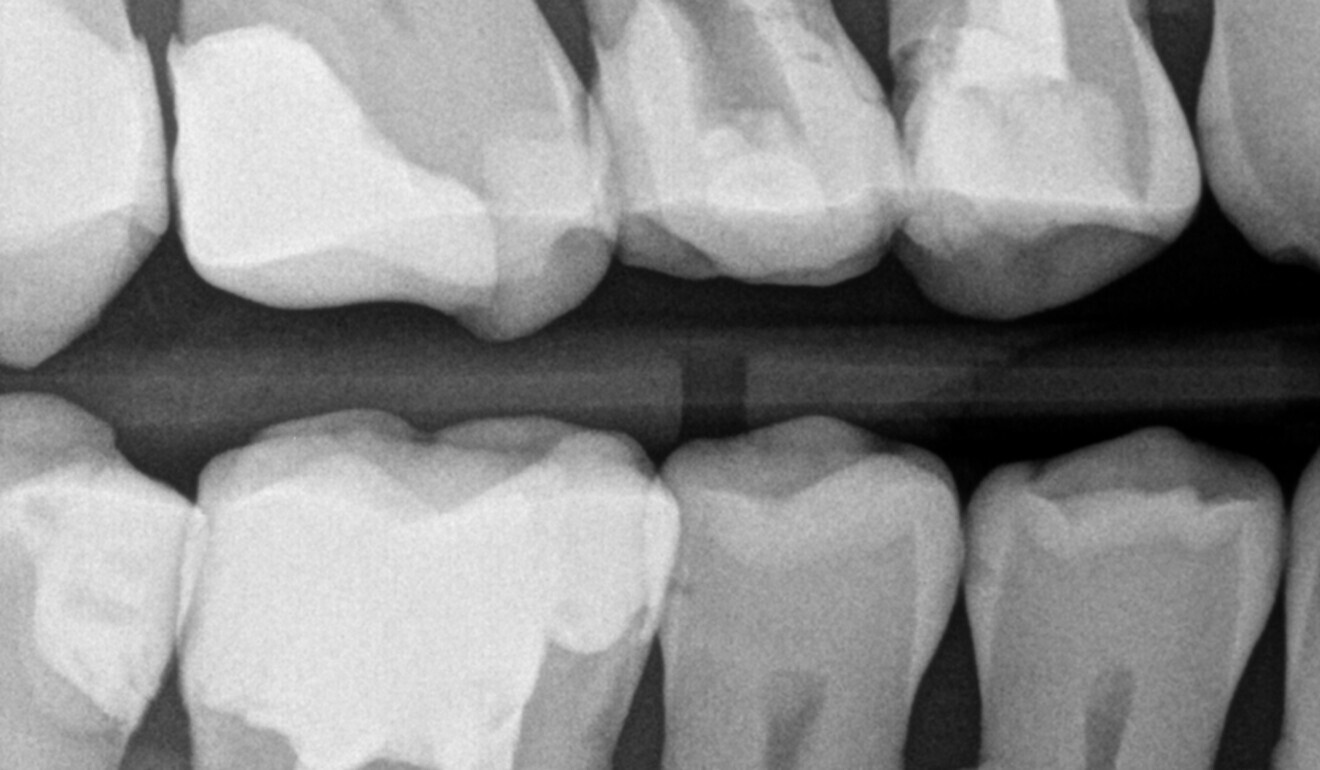

Fig. 3: Bitewing radiograph. Maxillary first molar with an overhang and negative profile of the distal wall. (Image: Kuraray Noritake Dental)

Based on a clinical and radiographic examination (Fig. 3), it was decided to restore the maxillary right first molar with a direct overlay, which would serve as a long-term temporary restoration for the duration of the orthodontic treatment. Once the local anaesthetic had been administered, a dental dam was placed in the upper right quadrant and the cusps of the affected first molar were reduced. For subgingival tooth preparation, the dental dam sheet was temporarily moved behind the maxillary second molar (Fig. 4). To obtain a good emergence profile of the restoration and a tight fit of the sectional matrix, a gingivectomy was performed with an electrical surgical knife (Fig. 5). The main advantages of a diathermic cut are instant tissue coagulation and haemostasis.9